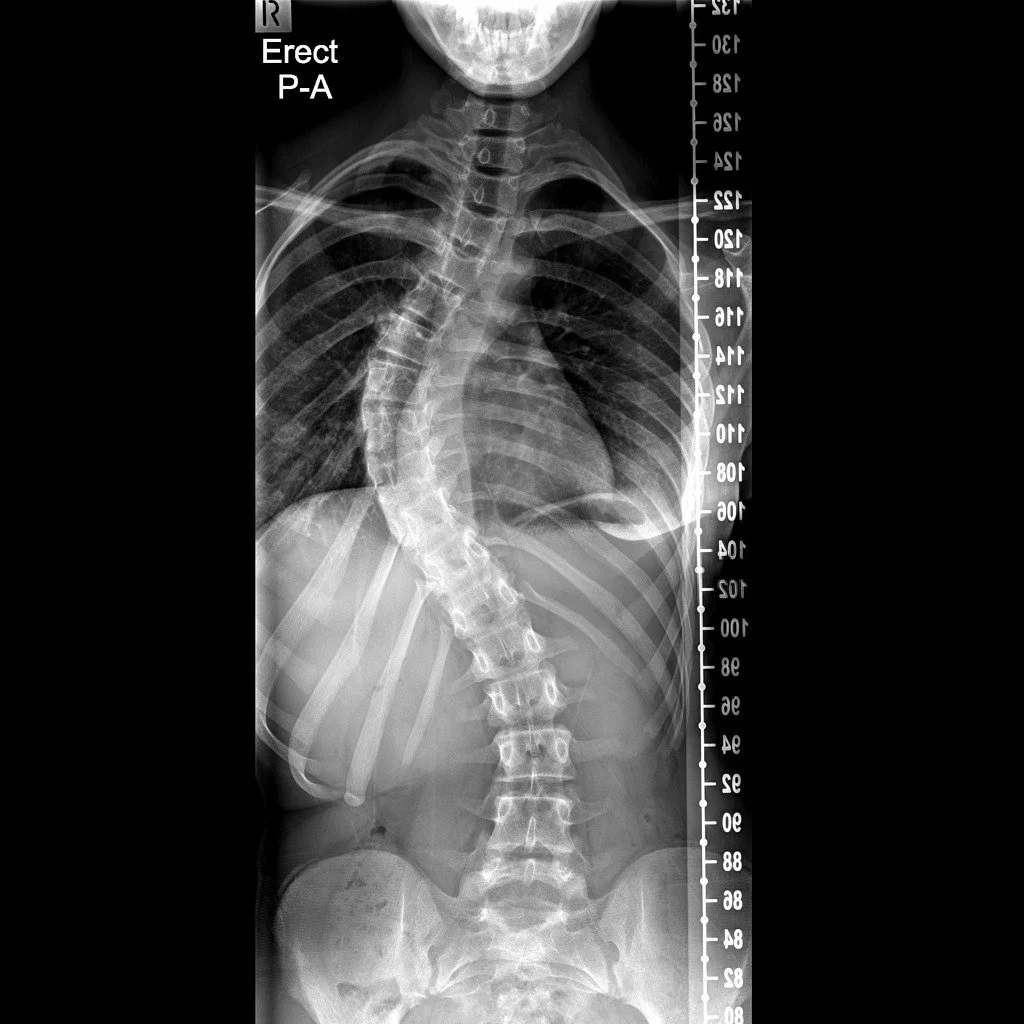

Son enfermedades de la columna que producen curvaturas anormales; comúnmente son desviaciones laterales de la columna (escoliosis) o arqueamientos exagerados (cifosis).

Atención a pacientes pediátricos con problemas en columna, ej. Escoliosis, cifosis, deformidades neuromusculares (parálisis cerebral infantil).